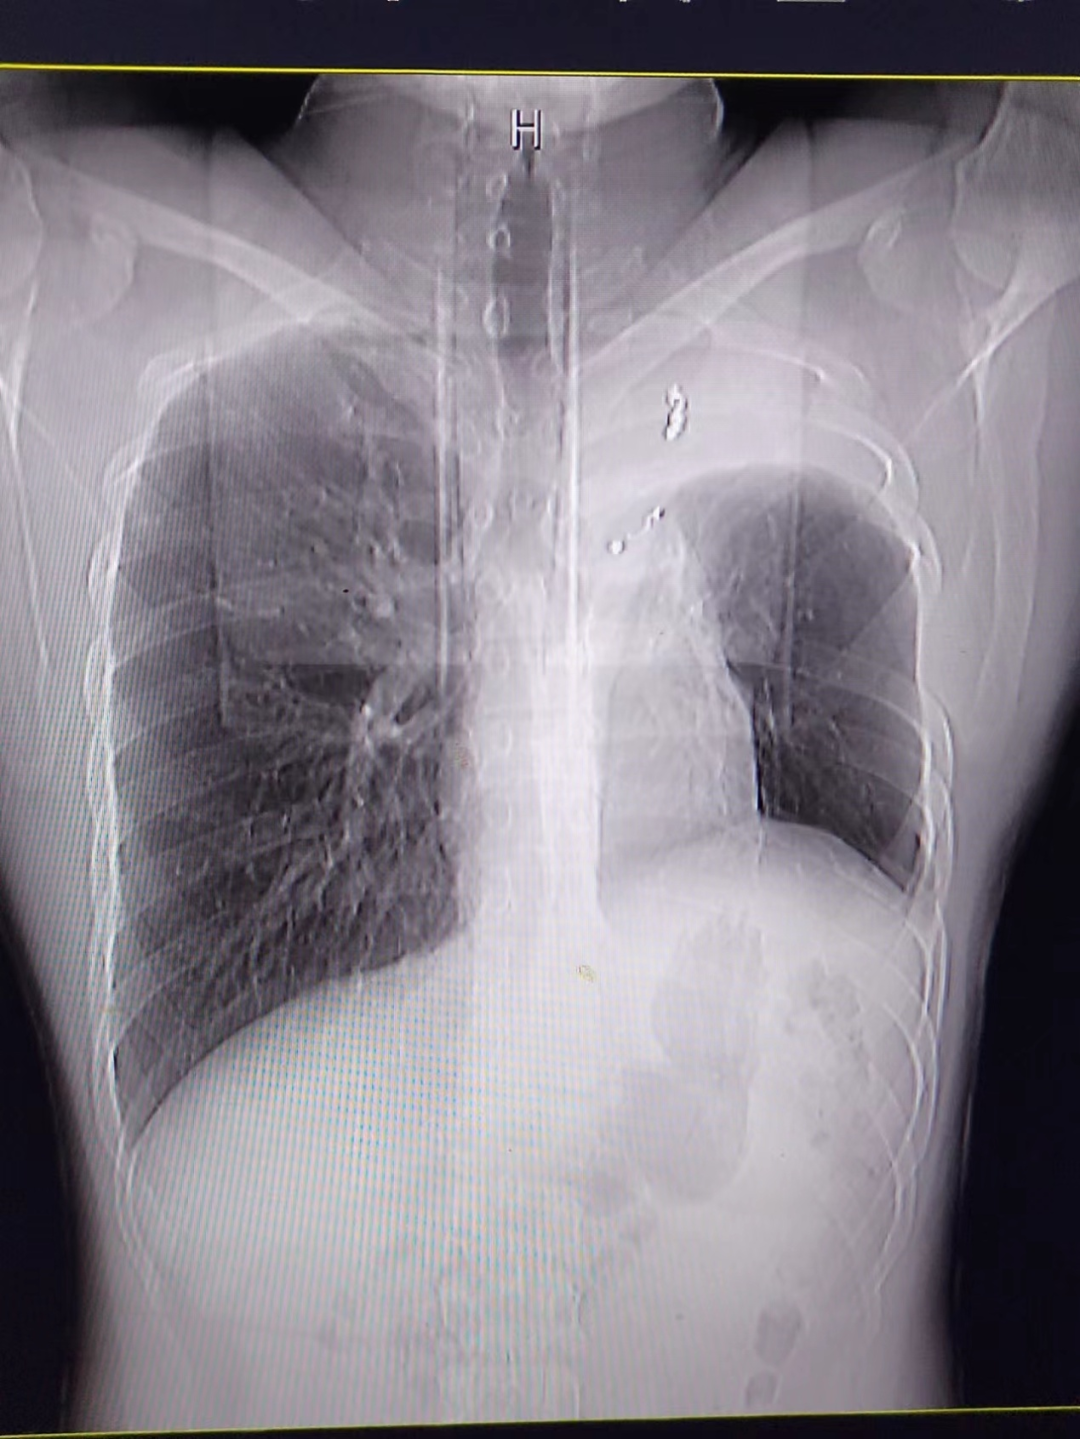

术后3月胸片,见残腔消失